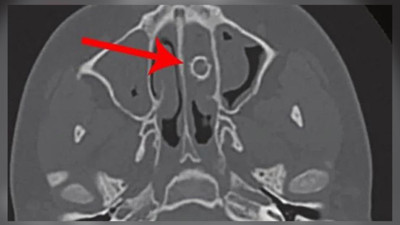

Kötü kokular geliyor deyince doktora gitti. Tam 8 yıl boyunca burnunda taşıdığı ortaya çıktı Amerika Birleşik Devletleri’nde eşi benzeri görülmemiş bir olay yaşandı. Yıllardır burun tıkanıklığı yaşayan genç, burnuna kötü kokular gelmesi üzerine doktora gitti. Gencin burnunda 8 yıl sonra havalı tabanca mermisi olduğu ortaya çıktı.